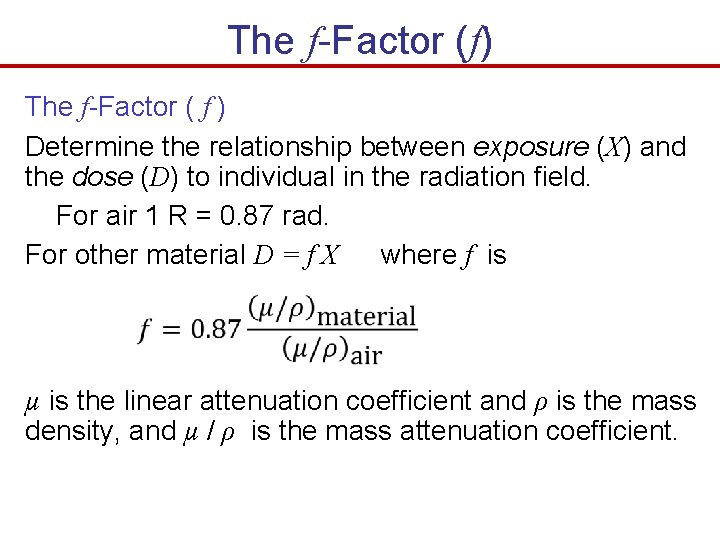

The f-Factor (f) The f-Factor ( f ) Determine the relationship between exposure (X) and the dose (D) to individual in the radiation field. For air 1 R = 0. 87 rad. For other material D = f X where f is µ is the linear attenuation coefficient and ρ is the mass density, and µ / ρ is the mass attenuation coefficient.